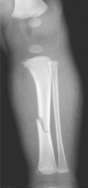

The material factual allegations of the amended complaint are as follows. Plaintiff was born on May 14, 1970. On repeated occasions during the first year of her life she was severely beaten by her mother and the latter’s common law husband, one Reyes. On April 26, 1971, when the plaintiff was eleven months old, her mother took her to the San Jose Hospital for examination, diagnosis, and treatment. The attending physician was defendant Dr. Flood, acting on his own behalf and as agent of the defendant San Jose Hospital. At the time, the plaintiff was suffering from a comminuted spiral fracture of the right tibia and fibula, which gave the appearance of having been caused by a twisting force. Plaintiff’s mother had no explanation for this injury. Plaintiff had bruises over her entire body. In addition, she had a non-depressed linear skull fracture which was then in the process of healing. Plaintiff demonstrated fear and apprehension when approached. Inasmuch as all plaintiff's injuries gave the appearance of having been intentionally inflicted by other persons, she exhibited the medical condition known as the battered child syndrome.

It is alleged that proper diagnosis of plaintiff's condition would have included taking X-rays of her entire skeletal structure, and that such procedure would have revealed the fracture of her skull. Defendants negligently failed to take such X-rays, and thereby negligently failed to diagnose her true condition. It is further alleged that proper medical treatment of plaintiff's battered child syndrome would have included reporting her injuries to local law enforcement authorities or juvenile probation department. Such a report would have resulted in an investigation by the concerned agencies, followed by a placement of plaintiff in protective custody until her safety was assured. Defendants negligently failed to make such report.

For example, the leading article by Kempe et al., op. cit., supra,[9] states that "A physician needs to have a high initial level of suspicion of the diagnosis of the battered-child syndrome in instances of subdural hematoma, multiple unexplained fractures at different stages of healing, failure to thrive, when soft tissue swelling or skin bruising are present, or in any other situation where the degree and type of injury is at variance with the history given regarding its occurrence . . . ." (Id., at p. 20.) Of the different types of fractures exhibited, an arm or leg fracture caused by a twisting force is particularly significant because "The extremities are the 'handles' for rough handling" of the child by adults. (Id., at p. 22.) The article also contains numerous recommendations to conduct a "radiologic examination of the entire skeleton" for the purpose of confirming the diagnosis, explaining that "To the informed physician, the bones tell a story the child is too young or too frightened to tell." (Id., at p. 18.) Finally, on the subject of management of the case it is repeatedly emphasized that the physician "should report possible willful trauma to the police department or any special children's protective service that operates in his community" (id., at p. 23) in order to forestall further injury to the child: "All too often, despite the apparent cooperativeness of the parents and their apparent desire to have the child with them, the child returns to his home only to be assaulted again and suffer permanent brain damage or death." (Id., at p. 24.)